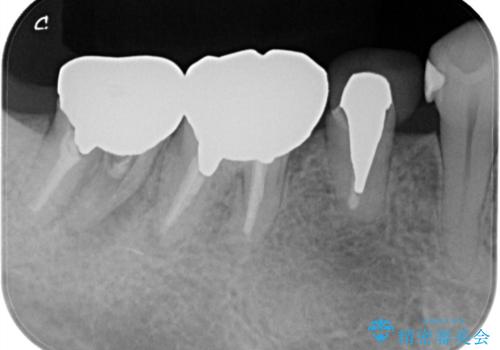

- 食事の度に、歯の中に物がつまるとのことで来院された患者様です。

精密検査を行った結果、歯が折れていたため保存は難しく、インプラント治療になりました。

インプラント治療をすることによってしっかりと噛めるようになりました。